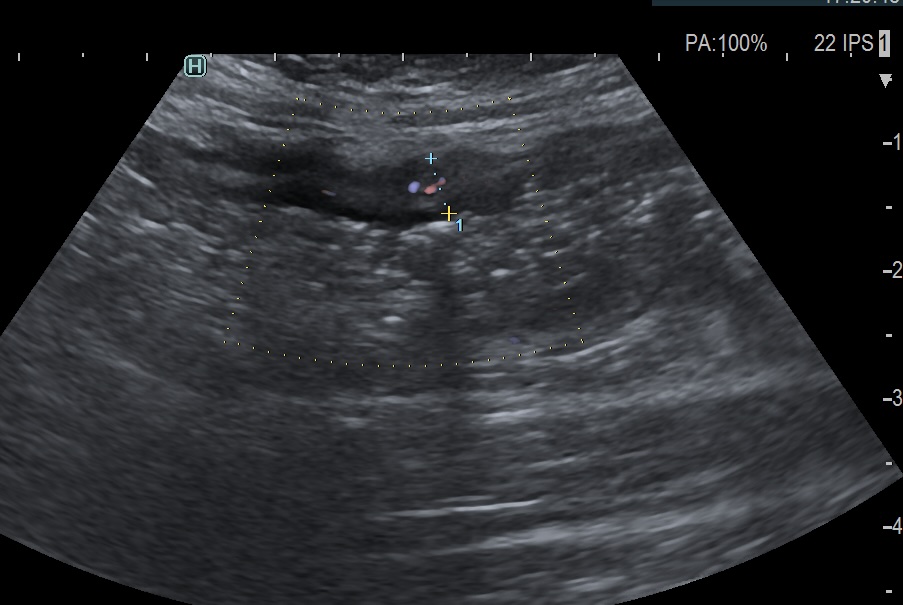

Activité Doppler limitée à la paroi, peu intense

- spots épars de petite taille

- Limberg 1 quelques signaux, courts, épars dans la paroi indiquant une faible vascularisation (= inflammation minime)